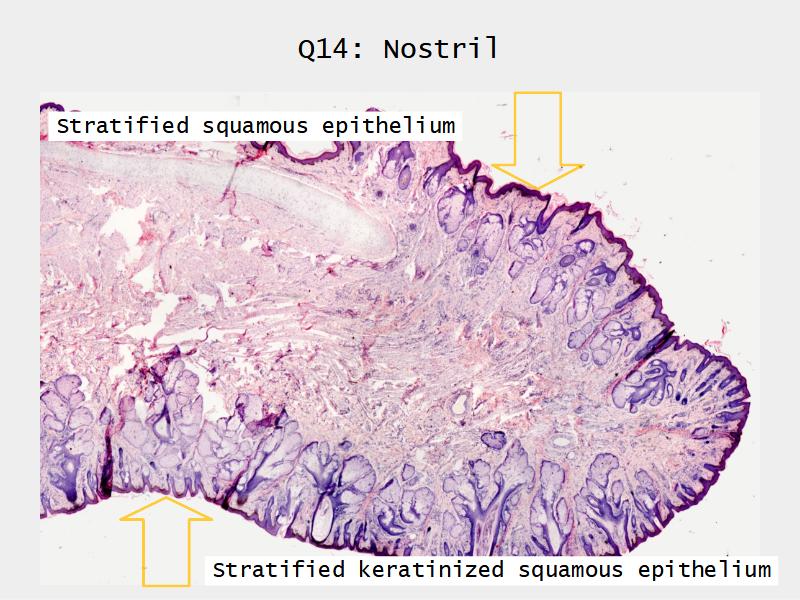

Slides: Respiratory System

- Slide 71: Nostril

Nostril